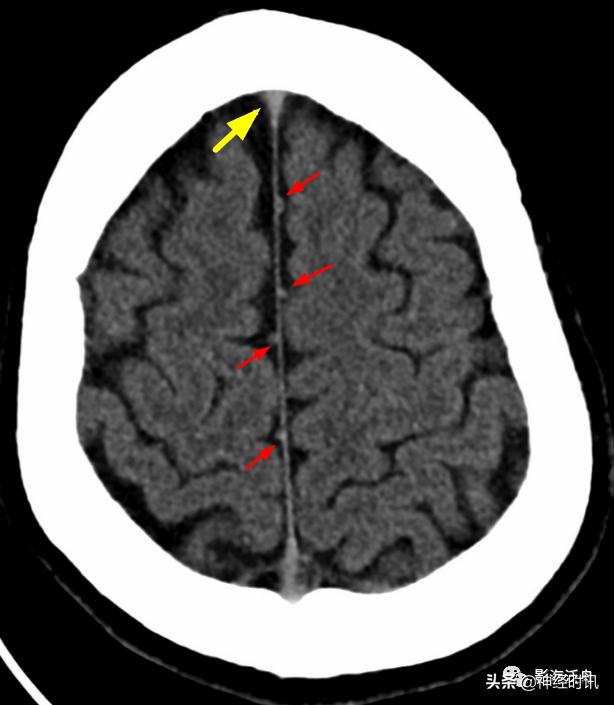

看完几个正常的,再来看一个异常的。2岁小孩,被电瓶车撞到后入院行头颅CT检查,大脑镰部多发短条状高密度影(红箭),注意和上面正常的大脑镰进行对比。

有些患者头颅CT平扫上份层面,大脑镰旁常可看到这种结节状高密度影(红箭),此系大脑上静脉的分支,不要误诊为少量蛛血。注意其密度与矢状窦相仿(黄箭),且均位于脑沟旁。